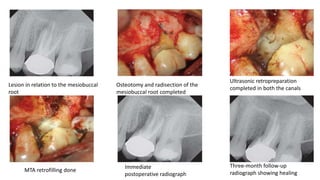

Lesion in relation to the mesiobuccal

root

Osteotomy and radisection of the

mesiobuccal root completed

Ultrasonic retropreparation

completed in both the canals

MTA retrofilling done

Immediate

postoperative radiograph

Three-month follow-up

radiograph showing healing